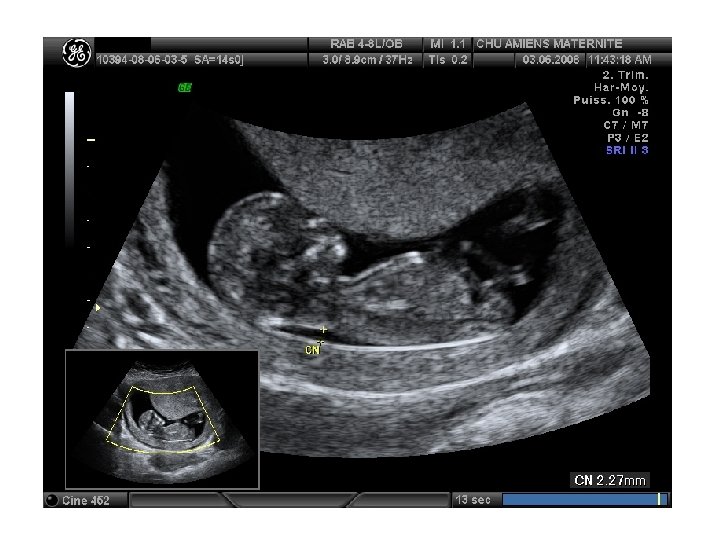

• Mesure de la clarté nucale - Définition de la clarté nucale = fine accumulation sous cutanée de liquide au niveau de la zone cervicale postérieure chez tous les fœtus entre 9 et 15 SA zone anéchogène entre la peau et les tissus musculaires

- Mesure : entre 11 SA et 13 SA+6 jours pour une LCC entre 45 et 84 mm - Critères de mesure : • entre 11 -14 semaines d'aménorrhée (SA) avec un idéal à 12 SA • un échographe rendant les mesures au dixième de mm près • coupe sagittale de l'embryon (celle de la mesure de la LCC) • embryon au repos (pas d'hyperextension) • image embryonnaire zoomée occupant au moins les 3/4 de l'écran • bien différencier membrane amniotique et tissu cutané cervical • limite interne du plan cutané à limite externe du plan sous-cutané • en effectuant 3 mesures en ne retenant que la plus élevée

- Intérêt : l’augmentation, audelà du 95° percentile, est associée à un risque accru d’anomalie chromosomique (21, 18, 13) + cloisons, débords latéraux = hygroma colli Clarté nucale Risque d’anomalie chromosomique > 3 mm X 3 > 4 mm X 18 >5 mm X 26 > 5, 5 mm X 36